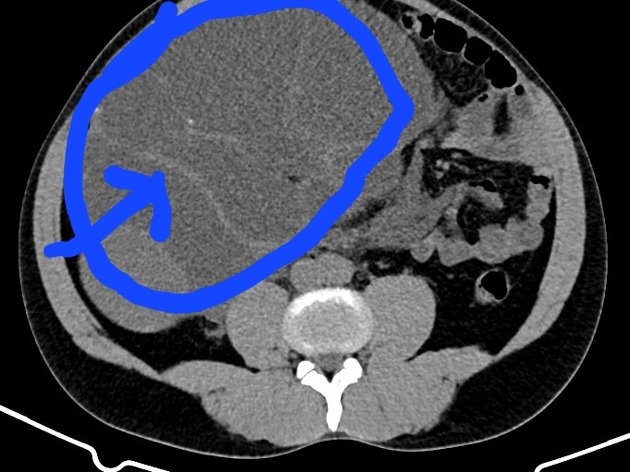

Seperti pd gambar di kiri bawah yg sy lingkari biru adalah ginjal yg bengkak hampir sama kayak kasus ini. (Ini bukan ct scan pasien sy)

Bandingkan dgn gambar kanan. Panah menunjukkan kedua ginjal yg normal (kanan & kiri).